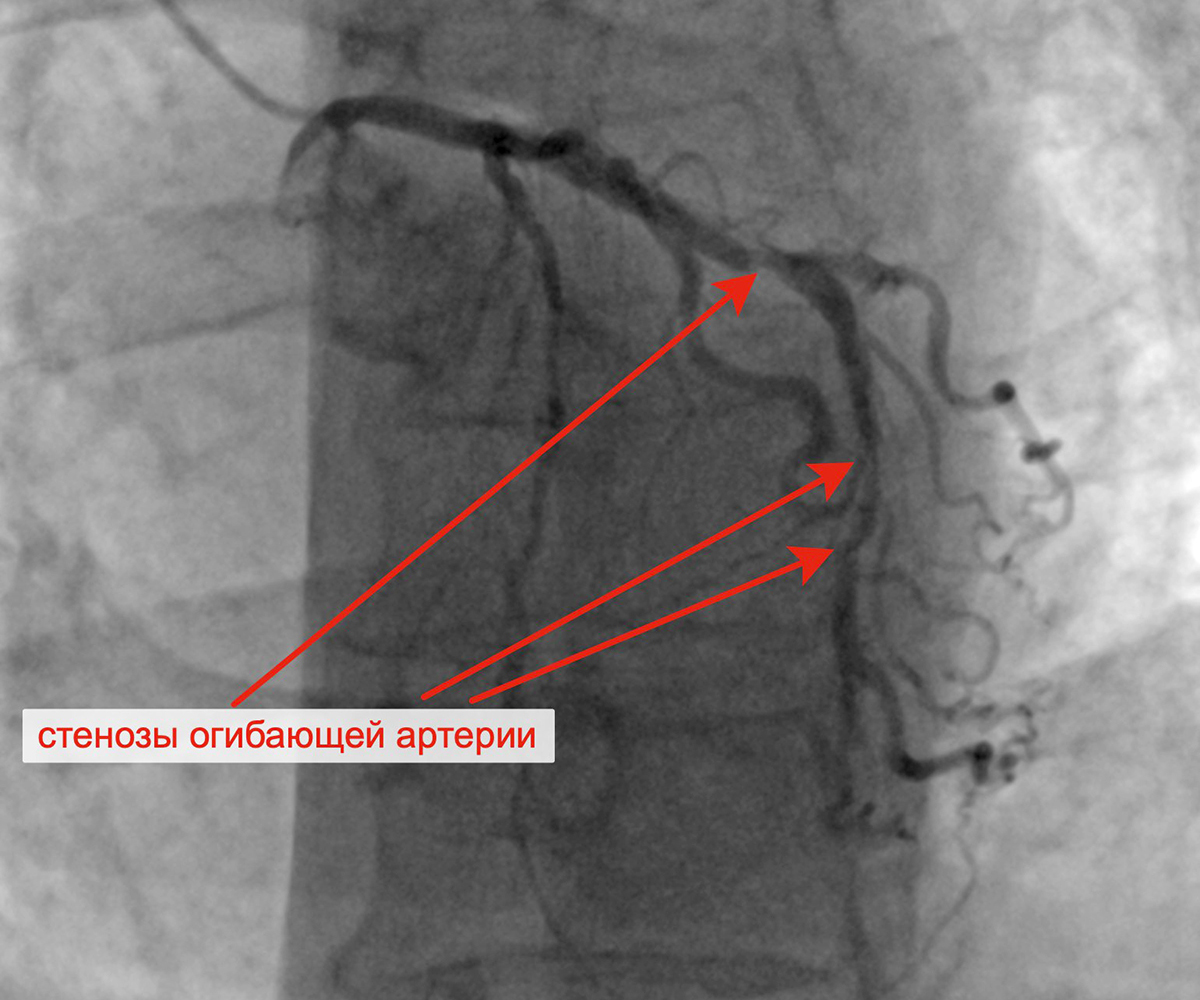

В марте 2023 г. в связи сохраняющейся одышкой, загрудинными болями при физической нагрузке пациент госпитализирован в кардиологическое отделение для решения вопроса о проведении следующего, третьего этапа реваскуляризации. Учитывая наличие ангинозных болей, результаты проведенных обследований (положительным стрессЭХО), коронарографии, наличие гемодинамически значимых стенозов коронарных артерий, принято решение о проведении баллонной ангиопластики и стентирования огибающей артерии (2 стента с лекарственным покрытием). Контрольная ангиография после успешного чрескожного коронарного вмешательства: стенты и ОА с ветвями проходимы, позиционирование стентов адекватное, диссекции или остаточного стеноза в стентированном сегменте ОА нет, кровоток TIMI 3 по ОА и всем ветвям.

Критические стенозы ОА Заведены проводники в ОА и ВТК

Имплантация первого стента в ОА Имплантация второго стента в ОА

Финальный результат имплантации 2 стентов в ОА